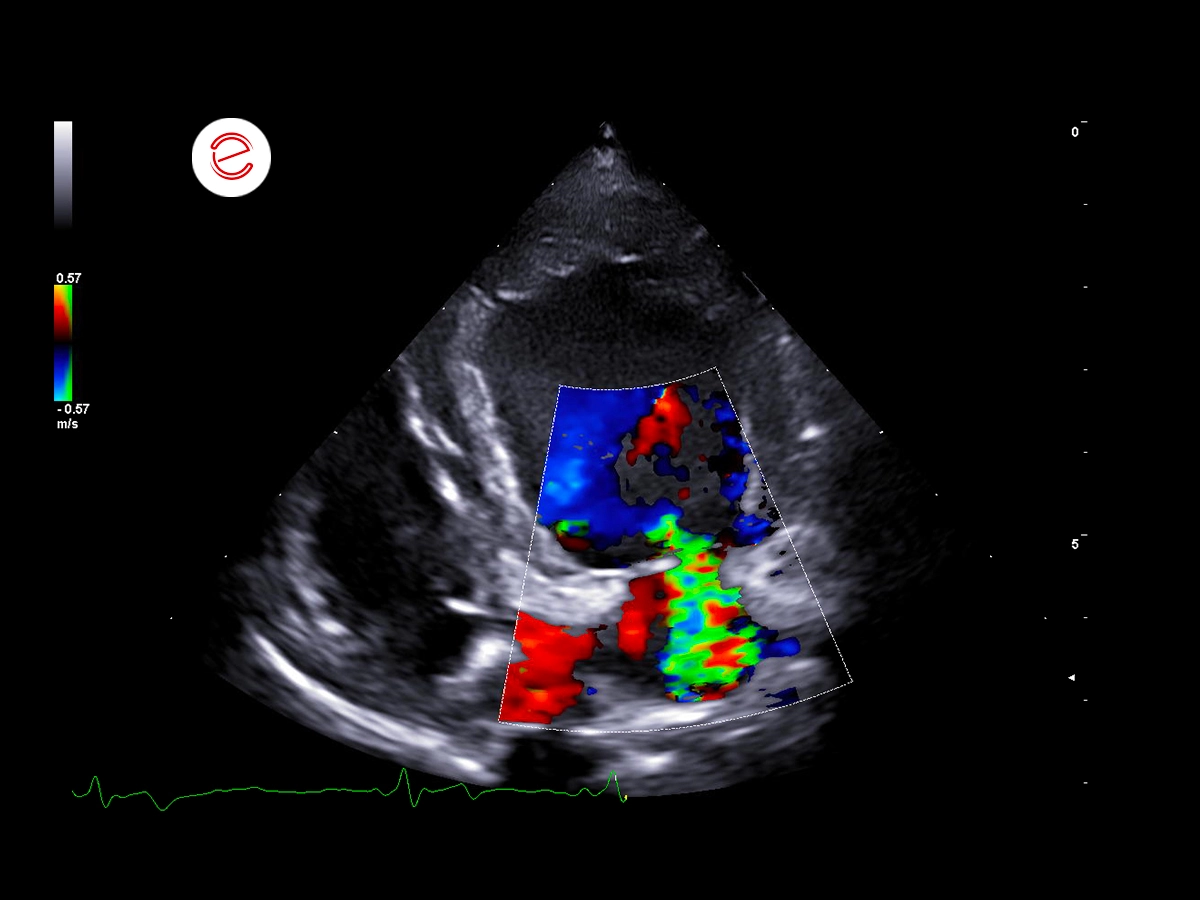

Color Doppler echocardiography revealed a mild-to-moderate mitral regurgitation jet, which was attributed to thickened mitral valve leaflets, suggesting degenerative changes consistent with myxomatous mitral valve disease. The recorded MR velocity was 1.5 m/s.